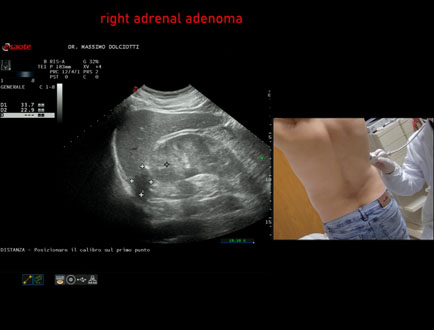

Ecografia del: 03/04/2026

Strumento: Esaote MyLab Eight

Sonda: Convex Multifrequenza 1-8 MHz

Età Paziente: M 49 anni

Motivazione dell'esame: riscontro occasionale

Commento all'esame: le immagini ed il video documentano in regione surrenalica destra, formazione ipoecogena a margini definiti, da ricondurre, come prima ipotesi, ad adenoma surrenalico.

Conclusioni: adenoma surrenalico destro (right adrenal adenoma).